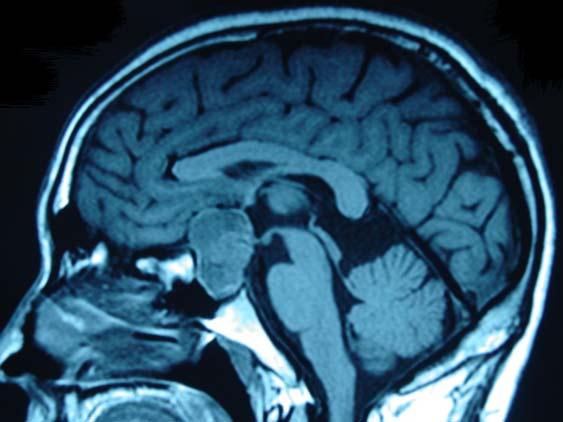

问题 男,47岁,头痛3年余,最近2个月感觉视力下降,MRI检查如图,最可能的诊断为()

选项 A.垂体瘤 B.颅咽管瘤 C.垂体囊肿 D.垂体腺瘤囊变 E.脑膜瘤

答案 D